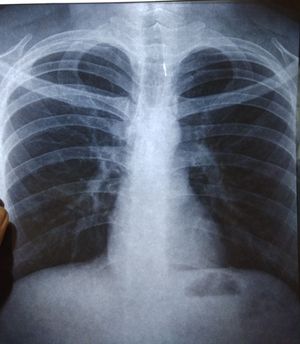

22 yr male presents with non productive cough which aggregated during night since 5 days, foreign body sensation in throat since 2 days..he is not allergic to any thing..x-ray done..what is your diagnosis??

Forgein body in trachea?

It appears to be something dense that is wedged in the trachea. The coughing would be ro remove it but I can't explain why he only coughs at night.

Looks like there is a foreign body in trachea?